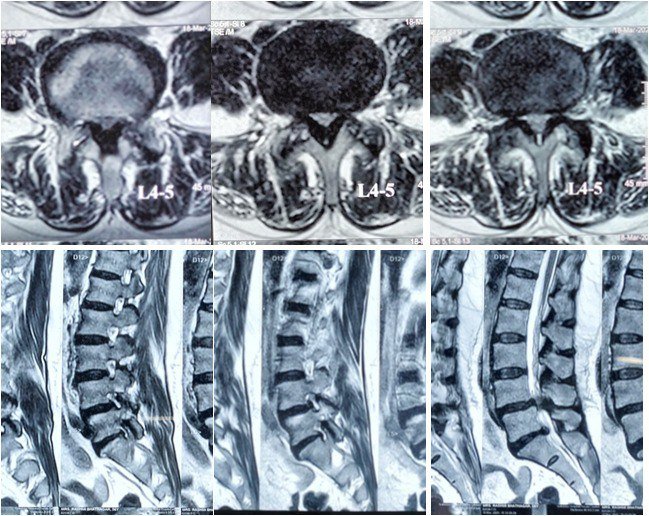

Before the Procedure

Before MIS TLIF, patients undergo a comprehensive evaluation including:

- Detailed clinical examination

- MRI / CT scan of the lumbar spine

- X-rays (including dynamic views)

- Blood tests and anesthetic assessment